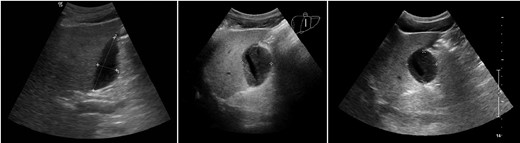

This patient remained in hospital for 1 month with postoperative complications. Ongoing leakage of bile prompted insertion of a percutaneous drain and endoscopic retrograde cholangiopancreatography with stent insertion. Ultrasound of the abdomen performed on Day 14 postoperatively demonstrated a collection with lobulated margins (Fig. 1). Concurrent hepatobiliary iminodiacetic acid scan confirmed that this represented an ongoing bile leak contained within the gallbladder fossa.

Ultrasound on postoperative Days 14 (left), 21 (middle) and 31 (right). Liver is on the left in each image, and the persistent collection is demonstrated within the gallbladder fossa.

Further ultrasound studies on Days 21 and 31 demonstrated an ongoing organizing collection (Fig. 1). He was discharged with the percutaneous drain in place, which was removed on Day 37 when drainage eventually ceased.